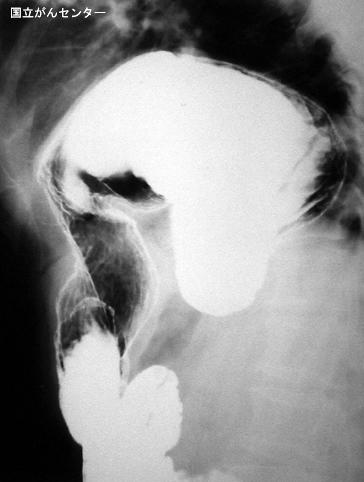

疾病(病理主体)的分类内脏器官形态异常/位置异常

部位(按器官分)胃(部位)/2个以上

检查方法X线